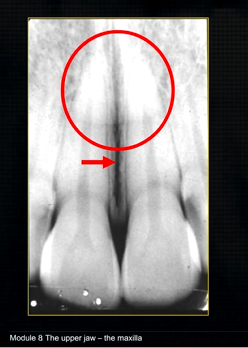

the upper jaw - the maxilla - what is circled in red?

the nasal cavity

what does this anterior periapical graph show?

oval radiolucent area between the central incisors - is it Infront of the teeth (buccally?) or is it behind them? - you can’t tell radiographically

but its shape and position is compatible with the palatally positioned with the nasopalatine formaina

more posteriorly - radiopacities indicate the nasal septum and floor of the nose

dense, thin , white line in the middle of the image is the nasal septum

radiolucency - nasal septum

lateral wall of the nose

maxillary air sinus

mid-palatal suture

this increased radiopacity is caused by the soft tissues at the tip of the nose - shadow - dense tissue